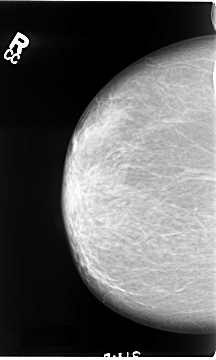

B_3064_1.LEFT_MLO

FILE: B_3064_1.LEFT_CC.OVERLAY

TOTAL_ABNORMALITIES 1

ABNORMALITY 1

LESION_TYPE MASS SHAPE IRREGULAR MARGINS SPICULATED

ASSESSMENT 4

SUBTLETY 4

PATHOLOGY MALIGNANT

TOTAL_OUTLINES 1

BOUNDARY